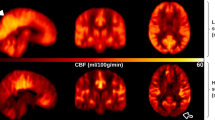

We reported all significant clusters in SPM analysis with a voxel-level peak threshold of P < 0.05 (FWE-corrected) over whole brain regions. Without adjusting for the global value, AD patients showed decreased absolute CBF in many brain areas, including the bilateral posterior cingulate, bilateral precuneus, bilateral inferior parietal lobule, bilateral inferior temporal gyrus, right superior temporal gyrus, right middle temporal gyrus, and right middle occipital gyrus, relative to the NC group (Table 3, Fig. 2).

Regional CBF changes in patients with AD from univariate analysis without adjusting for the global value in the identification cohort. Cool color indicates regions with decreased CBF in AD patients compared with NCs. A threshold of 3.23 (P < 0.001, uncorrected) was used to overlay SPM maps onto a standard MRI brain template. PCC posterior cingulate cortex

After ANCOVA normalization for the global value, both relatively decreased and relatively increased CBF were observed in the AD group in different regions (Table 4, Fig. 3). CBF in the bilateral posterior cingulate, bilateral middle cingulate, bilateral precuneus, bilateral inferior parietal lobule, and bilateral inferior temporal gyrus was relatively reduced in patients with AD compared to NCs. Regions with relatively increased CBF in the AD group included the right parietal postcentral gyrus, bilateral frontal precentral gyrus, right frontal supplementary motor area, and right putamen.

Regional changes in relative CBF after ANCOVA normalization for the global value in patients with AD in the identification cohort. Cool color indicates regions with relative decreased CBF, and warm color indicates regions with relative increased CBF in AD patients compared to NCs. A threshold of 3.23 (P < 0.001, uncorrected) was used to overlay SPM maps onto a standard MRI brain template. MCC middle cingulate cortex, PCC posterior cingulate cortex

Global value measured from the CBF map was significantly reduced in the AD group compared to NCs (32.7 ± 5.6 vs 36.7 ± 5.0 ml/100 g/min, t = 3.065, P < 0.01; Fig. 5A). Sample plots for the major regions with decreased relative CBF in the AD group, including the right precuneus, left posterior cingulate, left inferior parietal lobule, right inferior parietal lobule, and right inferior temporal gyrus, are shown in Fig. 5B–F. ROC curves were generated for both global and relative regional CBF values in distinguishing patients with AD from NCs (Supplementary Fig. 1). The area under the ROC curve was 0.72 (95% confidence interval 0.60–0.85), with a sensitivity of 65.63%, a specificity of 71.88% for global CBF value. In terms of relative regional CBF values, the left posterior cingulate showed the highest sensitivity (100%) and specificity (100%) for differentiating patients with AD from NCs.

Difference in global CBF value and relative CBF values for five sample regions between the AD group and the NC group in the identification cohort. A The comparison of global value between AD patients and NCs from the CBF map. B–F The comparisons of relative values in the right precuneus (3, − 66, 44), left posterior cingulate (− 2, − 48, 32), left inferior parietal lobule (− 36, − 62, 45), right inferior parietal lobule (53, − 41, 51), and right inferior temporal gyrus (59, − 44, − 15) between AD patients and NCs, obtained post hoc within a spherical volume of interest (4 mm radius). *P < 0.01; ***P < 0.001